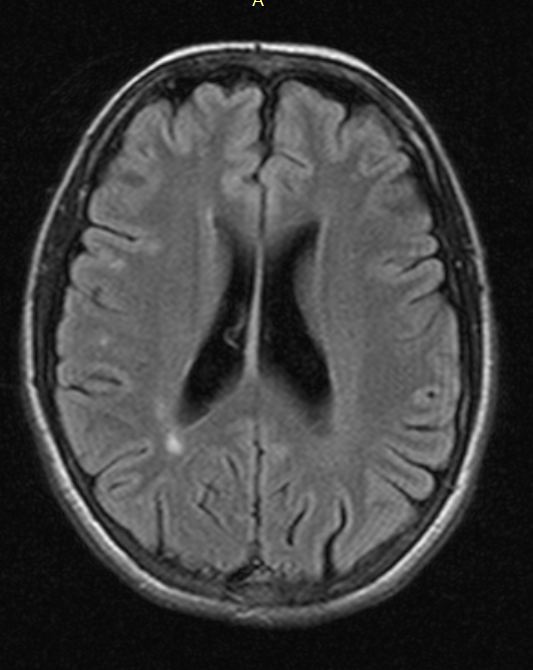

Fazekas grades. Перивентрикулярный лейкоареоз на кт. Fazekas 1. Фазекас мрт. Лейкоареоз Fazekas 1 что это.

Fazekas grades. Перивентрикулярный лейкоареоз на кт. Fazekas 1. Фазекас мрт. Лейкоареоз Fazekas 1 что это.

Fazekas grades. Лейкоареоз Fazekas 1 что это. Очаги Фазекас мрт. Лейкоареоз степени по Fazekas. Лейкоареоз головного мозга на кт.

Fazekas grades. Лейкоареоз Fazekas 1 что это. Очаги Фазекас мрт. Лейкоареоз степени по Fazekas. Лейкоареоз головного мозга на кт.

Fazekas grades. Лейкоареоз Fazekas 1 что это. Лейкоареоз степени по Fazekas. Fazekas 1 что это такое мрт. Лейкоареоз мрт степени.

Fazekas grades. Лейкоареоз Fazekas 1 что это. Лейкоареоз степени по Fazekas. Fazekas 1 что это такое мрт. Лейкоареоз мрт степени.